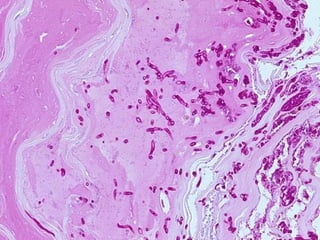

• #106 PAS stain of hyphae

• #107 PAS stain of hyphae

TINEAS… • …Capitis(Scalp ringworm) • …Barbae • …Corporis (Ringworm) • …Cruris (Jock itch) • …Pedis (Athlete’s foot) • …Onychomycosis (nail)

TINEAS • Trichophytonspecies • Microsporum species • Epidermophyton species